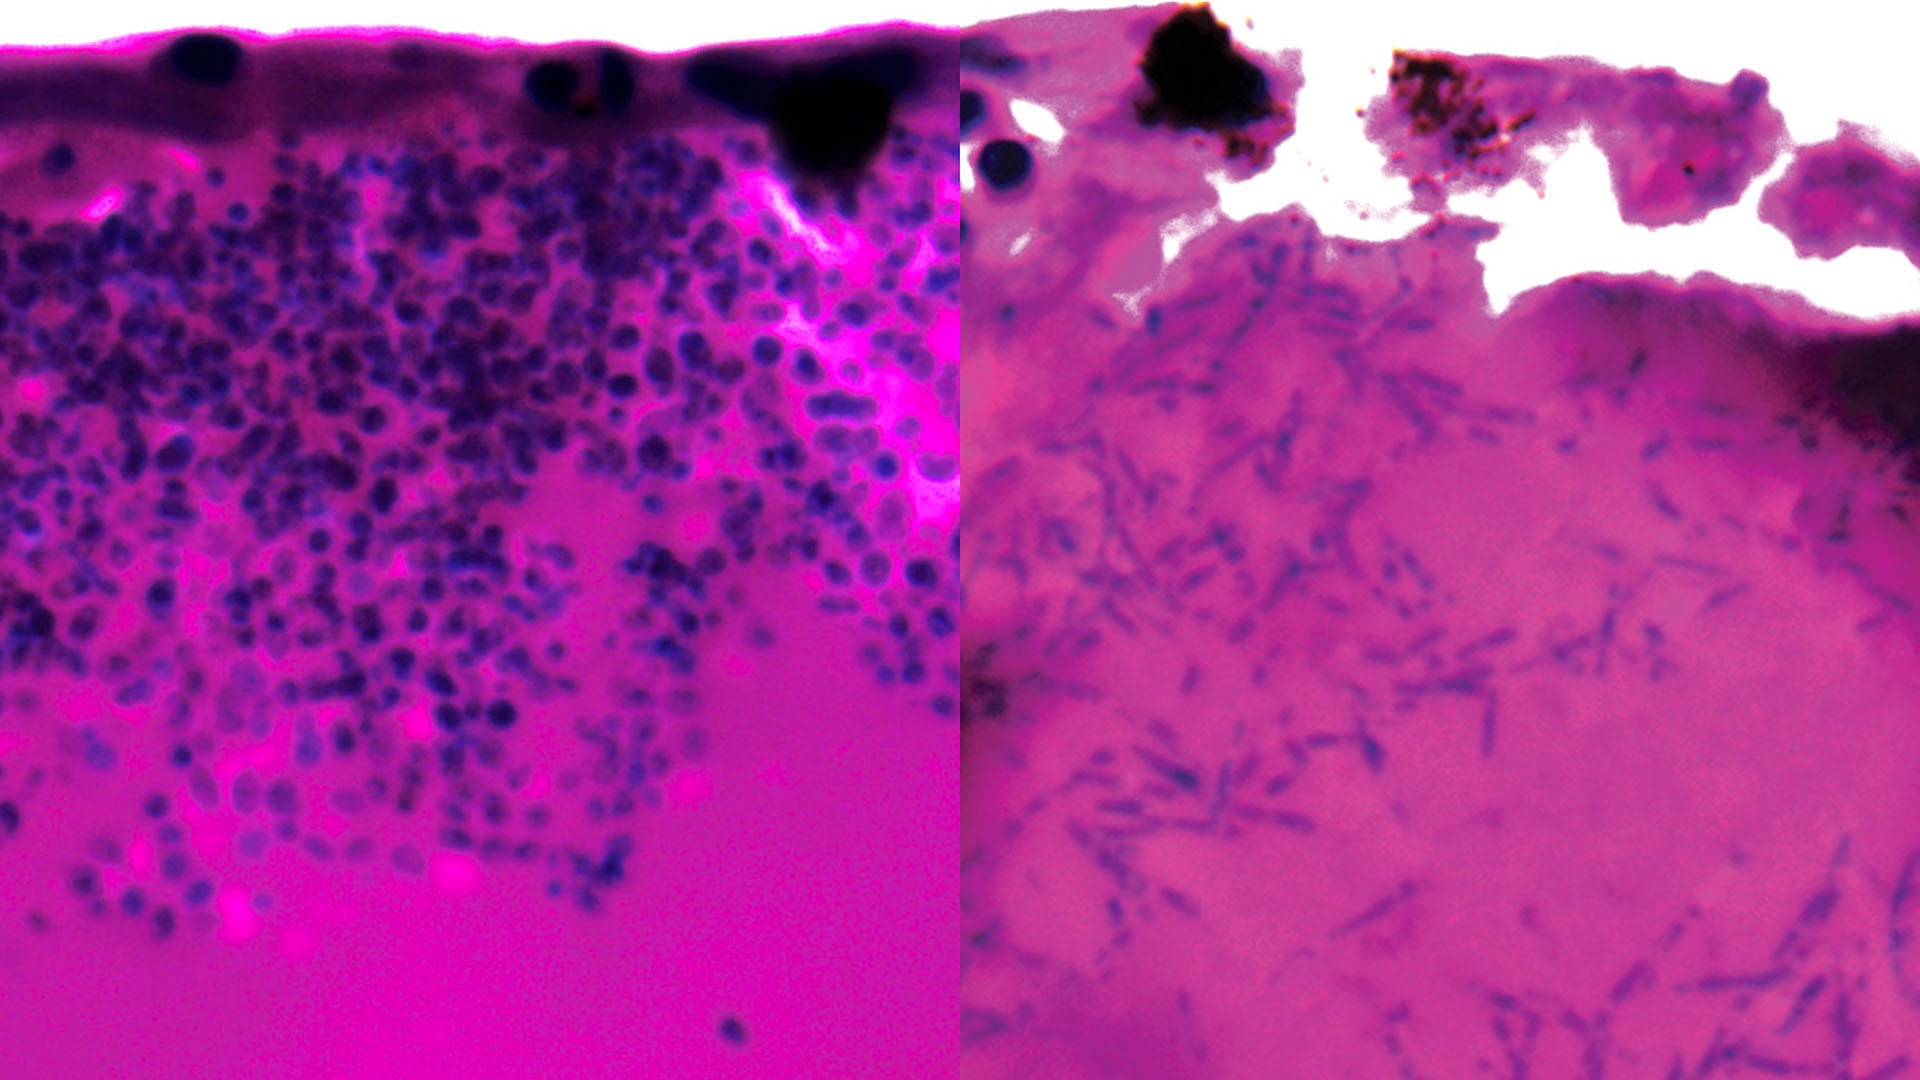

El equipo eligió al pez killi árabe, cuyas larvas soportan la temperatura corporal humana, para investigar la infección. Así pudieron mirar bajo el microscopio cómo responde el hongo minuto a minuto ante los desafíos del organismo vivo.

Candida auris se transforma en filamentos, es decir, estira sus células para buscar nutrientes, lo que facilita su expansión. Esta estrategia le da ventaja y lo vuelve más difícil de combatir con los tratamientos habituales.

Durante la infección, los investigadores observaron que ciertos genes capturan moléculas que buscan hierro y las introducen en las células.

La técnica de observar todo en tiempo real permitió registrar cómo el hongo esquiva al sistema inmune y se adapta rápidamente a cualquier cambio dentro del organismo del huésped.